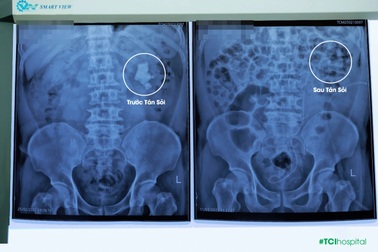

Sỏi thận 6cm cùng 3 viên sỏi khác được lấy sạch trong một lần điều trịSau ba lần can thiệp mổ mở, ông N.H.T (sinh năm 1962, Sơn Tây) không ngờ có ngày sẽ được "giải tỏa" ổ sỏi 4 viên lấp kín đài bể thận trong một lần tán sỏi qua da hạn chế xâm lấn.